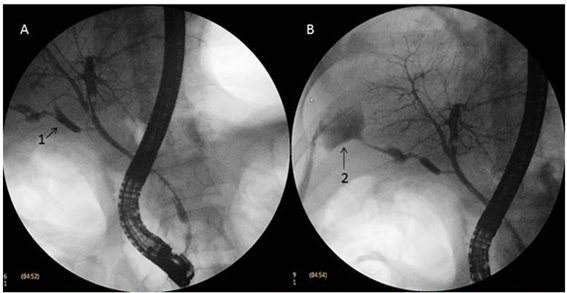

- La colangiopancreatografía retrógrada endoscópica es para determinar el origen de la fuga. Este procedimiento es tanto diagnóstico como terapéutico.

La colangiopancreatografía retrógrada endoscópica (CPRE ) se recomienda como tratamiento. Puede ser con esfinterotomía sola, colocación de endoprótesis solo o terapia combinada. Los tipos A, C y D se tratan normalmente con esta modalidad.